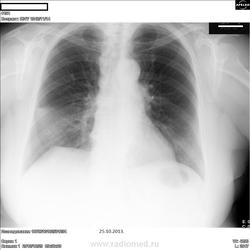

Что-то не даёт мне согласиться с пневмонией.То ли отсутствие бокового,то ли подпаянный купол.Да и не совсем "инфильтративно".Честно говоря,не дал бы заключения без бокового или динамики.Рака боюсь.

Возможно, в междолевой щели справа немного жидкости.

Ну,так выпот в междолевой щели,да и передний синус несвободен.Ждём динамику,должно бы рассосаться.

Пока, так называемый среднедолевой синдром, может и ателектаз.

Прямая проекции опровергает наличие ателектаза.

Рассосалось.Посчитаем пневмонией,осложнённой выпотом от 25.10 с положительной динамикой.